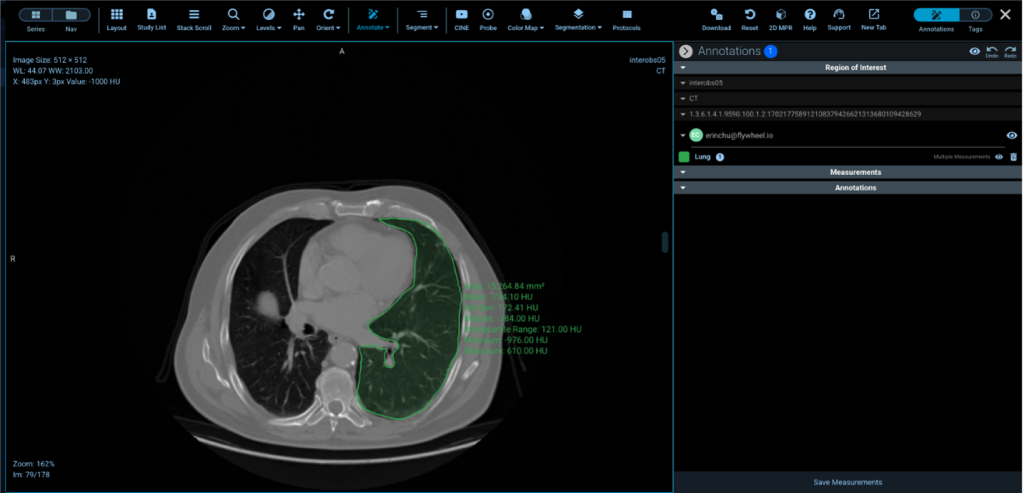

You can then visualize your data in Flywheel’s zero footprint radiology viewer as shown in Figure 5. The reviewer allows users to view, annotate, and segment medical images.

Figure 5 – View Health Image